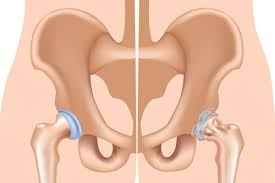

Introduction to Robotic Orthopedic Surgery Robotic orthopedic surgery in Kanker offers a modern and highly precise approach to treating complex bone and joint conditions. Orthopedic problems such as arthritis,...

Introduction to Robotic Joint Replacement Robotic joint replacement in Kanker represents a major advancement in orthopedic surgery, offering higher precision, improved outcomes, and faster recovery compared to traditional techniques....